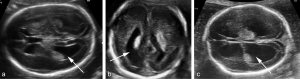

Giãn não thất thai nhi là gì? Định nghĩa: Giãn não thất là tình trạng [...]

GIÃN NÃO THẤT THAI NHI? TỔNG QUAN Y KHOA VÀ HƯỚNG DẪN LÂM SÀNG

GIÃN NÃO THẤT LÀ GÌ: NHỮNG ĐIỀU CẦN BIẾT ĐỂ CHA MẸ KHÔNG QUÁ LO LẮNG

Khi đi siêu âm thai định kỳ, nhiều phụ huynh không khỏi lo lắng khi [...]